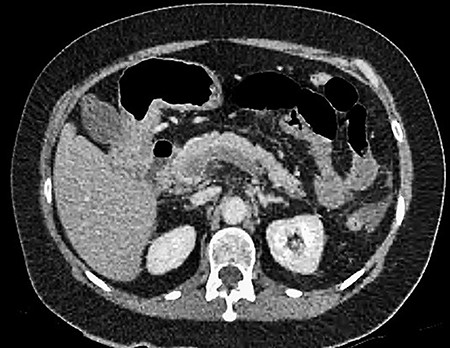

A 61-year-old female presented to a regional hospital with a 3-week history of intermittent diarrhoea, vomiting and generalized abdominal pain. She had a diffusely tender abdomen but was not peritonitic, and was shocked with a heart rate of 110 beats per minute, blood pressure of 89/45 mmHg and was peripherally cool. Her blood tests revealed a lactate of 7.2 mmol/L, which worsened to 7.8 mmol/L during resuscitation with intravenous fluids, and white cell count was 30.9 × 109/L, with an international normalized ratio (INR) of 1.4. She had an acute kidney injury with a creatinine of 119μmol/L and estimated glomerular filtration rate (eGFR) of 43 mL/min/1.73m2. Computed tomography (CT) revealed extensive thickened loops of non-enhancing small bowel with pneumatosis, moderate free fluid and a large splenic infarction. There was extensive thrombosis of the splenic vein and superior mesenteric vein extending into the portal vein to the level of the porta hepatis. Her background history included factor V Leiden and protein S deficiency, for which she had been non-compliant with warfarin during this illness. She had no surgical history (Figs. 1–5).

CT showing complete occlusion of the portal vein at the level of the porta hepatis.